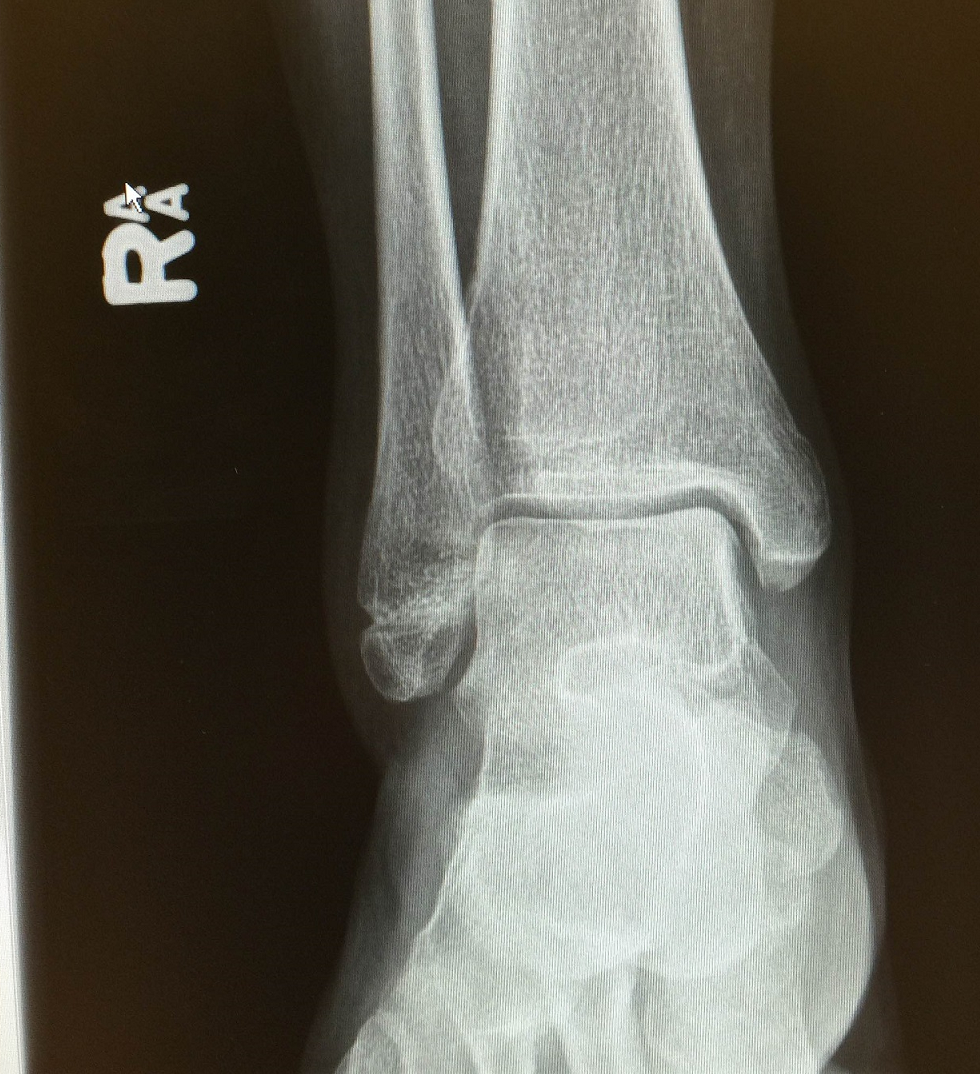

左脚踝骨折,骨裂,手术上钢板

请医生看看我这张脚背x光片有没有问题,如骨裂骨折等问题.